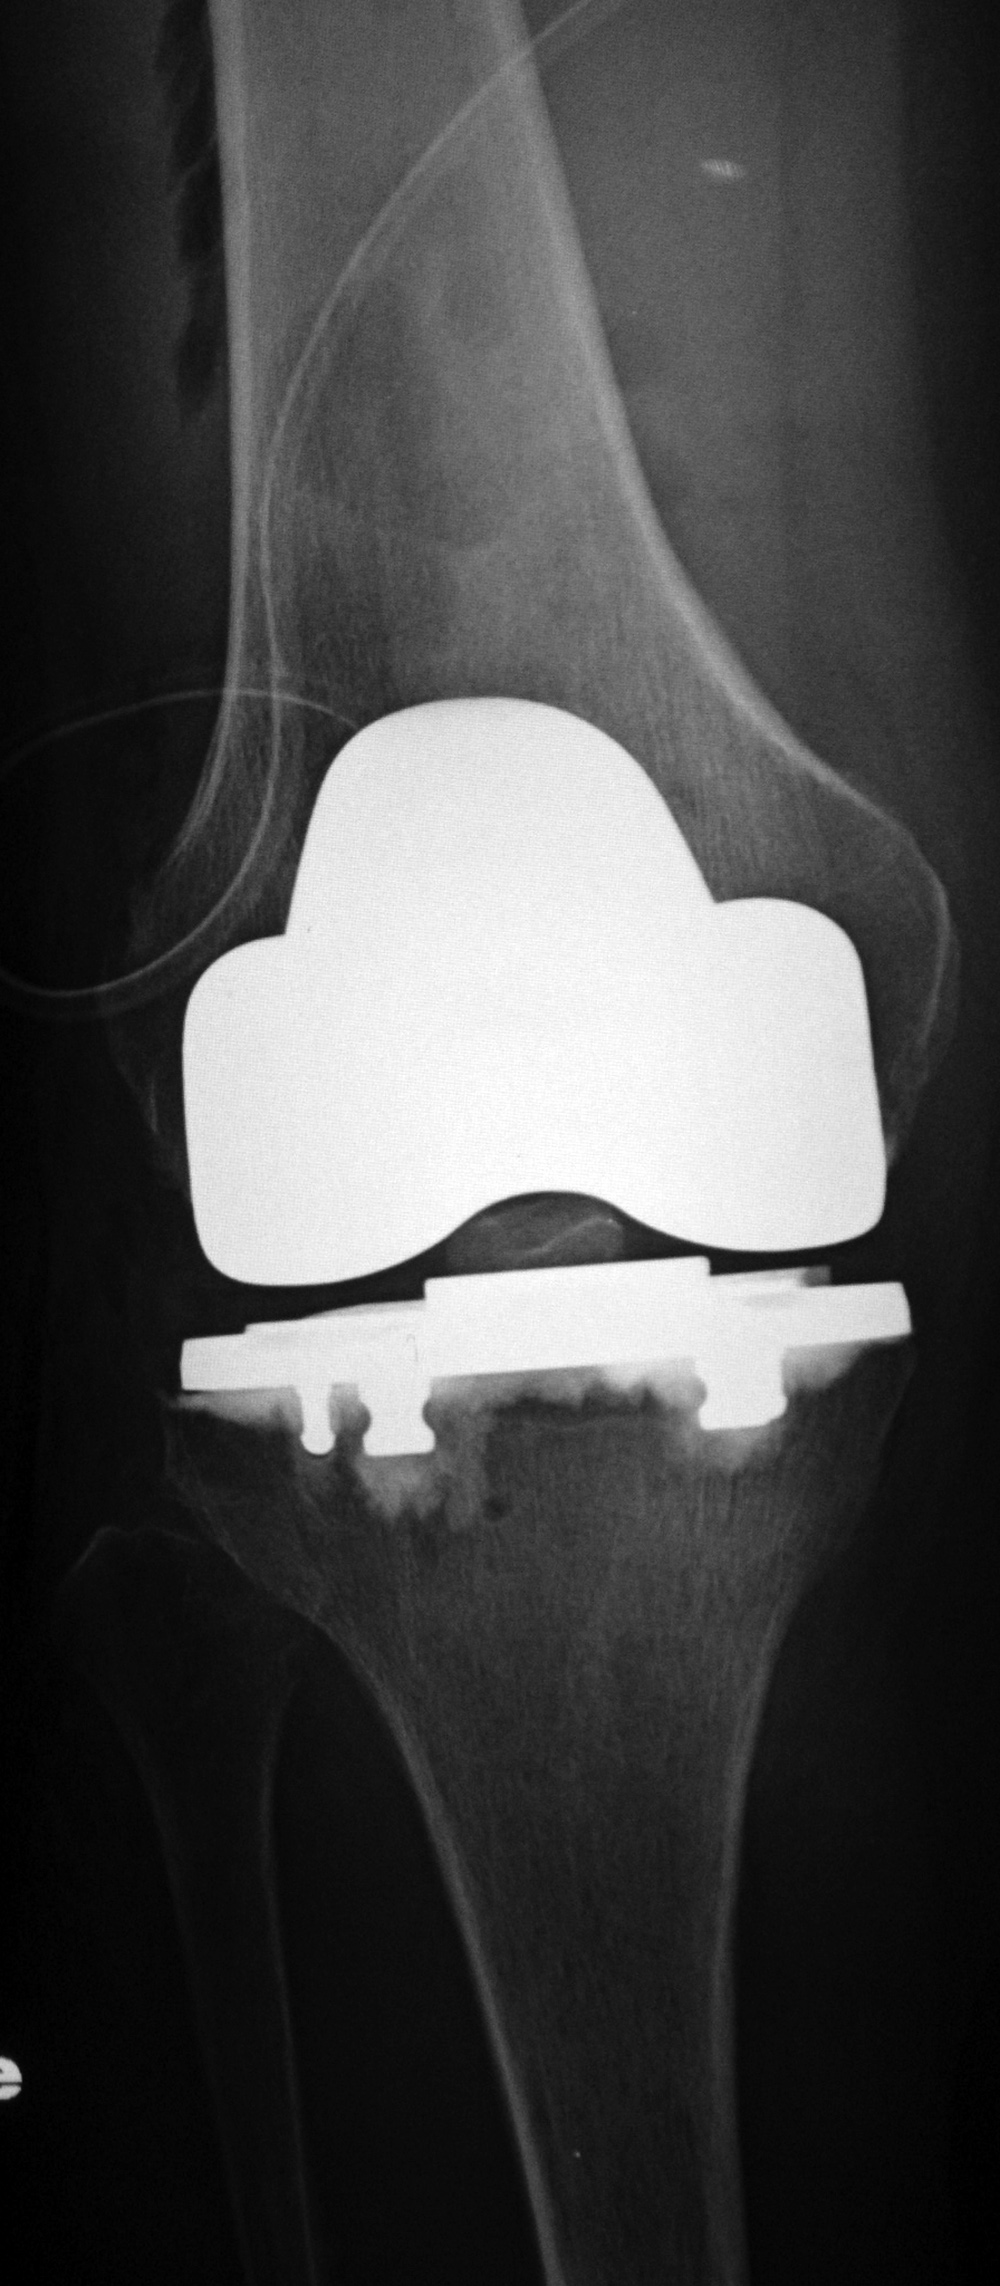

| 68 year-old woman treated for severe left knee osteoarthritis |

Note the large distal femoral box. There is a surgical drain in the suprapatellar space. |